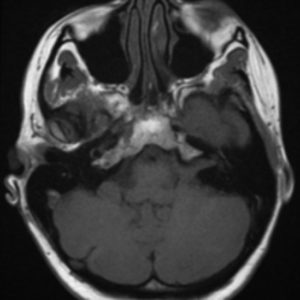

U dây VIII

Lượt xem: 140» 24-11-2018 -

U dây VIII

Lượt xem: 131» 24-11-2018 -

U dây VIII

Lượt xem: 143» 24-11-2018 -

U dây VIII

Lượt xem: 155» 24-11-2018 -

U dây VIII

Lượt xem: 124» 19-11-2018 -

U dây VIII

Lượt xem: 159» 05-11-2018 -

U dây VIII

Lượt xem: 239» 30-10-2018 -